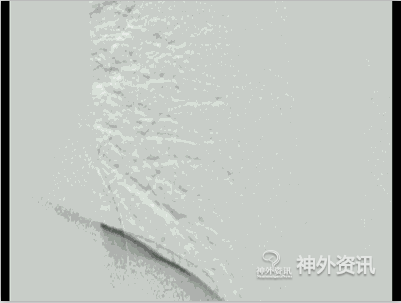

图9: E. 2D-DSA正侧位动态影像。

图9: F. 2D-DSA正侧位动态影像。

图9: H. 术后2D-DSA正侧位动态影像,瘘口已消失术后双下肢肌力恢复至五级。

图9: I. 术后2D-DSA正侧位动态影像,瘘口已消失术后双下肢肌力恢复至五级。